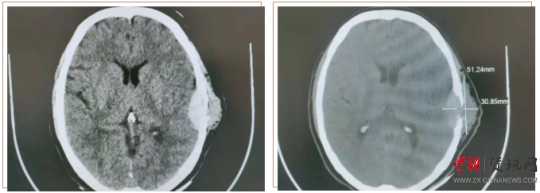

患者王某,女,58歲。半年前,患者用手觸摸頭部左耳上側(cè)時(shí),發(fā)現(xiàn)一個(gè)小腫物,如花生米大小,當(dāng)時(shí)沒太在意,十幾天前發(fā)覺腫物突然增大,由原來的1cm左右增大至5cm左右,且有壓痛感。于是來到上蔡縣人民醫(yī)院就診。神經(jīng)外科副主任楊學(xué)義接診后,安排患者做顱腦CT檢查,結(jié)果顯示:左側(cè)顳部占位侵犯腦膜及顱骨骨板,需要手術(shù)治療。遂收入神經(jīng)外科,經(jīng)過充分的術(shù)前討論,制定周密的手術(shù)方案后,由神經(jīng)外科主任周學(xué)良、副主任楊學(xué)義、主治醫(yī)師商文山、楊慶華歷時(shí)3個(gè)小時(shí),成功將患者左側(cè)顳部5×4cm腫瘤完全切除,同時(shí)行“硬腦膜修補(bǔ)、顱骨修補(bǔ)手術(shù)”,術(shù)中精準(zhǔn)解剖,精細(xì)操作,避免了血管及神經(jīng)等副損傷。術(shù)后顱腦CT掃描顯示:腫瘤完全切除,無腫瘤組織殘留;颊攥F(xiàn)已痊愈出院,未出現(xiàn)神經(jīng)功能障礙。目前正在隨訪中。

顱腦 CT 掃描顯示(下圖):左側(cè)顳部占位侵犯腦膜及顱骨骨板。